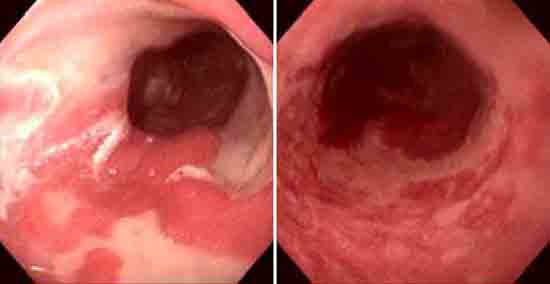

Barrett食管可以做哪些检查

导语 食管下段的鳞状上皮被柱状上皮覆盖,称Barrett食管,又称巴雷特食管。 查看更多